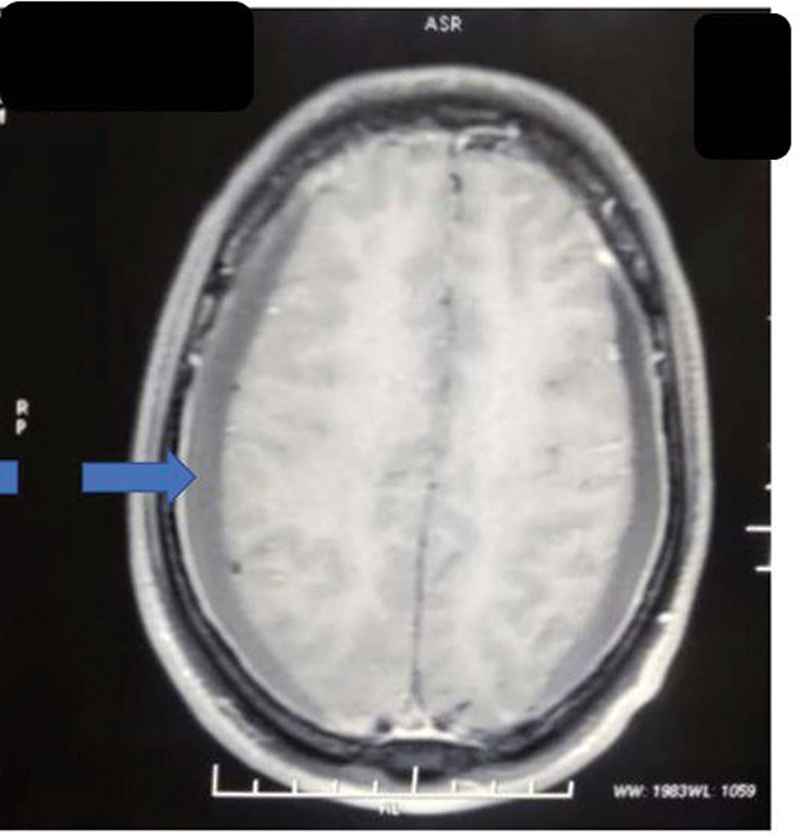

Cerebrospinal fluid (CSF) provides buoyant support to the brain and spinal cord. According to the Monroe-Kellie doctrine, confined space in the cranium causes any change in CSF volume contributing to significant intracranial pressure changes, which cause a variety of pathologies and symptoms. We, hereby, present a case of a 33-year-old gentleman who after a motorcycle road traffic accident came to us complaining of persistent headache and neck pain with subdural hematoma (SDH) like presentation, clinically and radiologically, but was reevaluated and diagnosed as traumatic intracranial hypotension and successfully managed surgically after that. Hygromas are believed to be compensatory enlargement of the subdural space due to the loss of CSF volume. The true mechanism of the development of SDH or hygroma due to intracranial hypotension is yet to be hypothesized but provisionally described by a rupture of the bridging veins by being pulled away from the dura because of the low intracranial pressure (ICP) and brain descent. Many prior cases in the literature are shown to have treated the patient with immediate burr hole and decompression of SDH, but this paradoxically worsens the patient due to further lowering of ICP. The causes of prolonged postconcussion headaches are often unidentified, of which intracranial hypotension caused by a CSF leak is potentially under-recognized. In such cases, bilateral SDH with mass effect must be ruled out of any CSF leak before attempting the lifesaving decompressive surgery, as it may paradoxically lead to further morbidity and mortality of the patient.